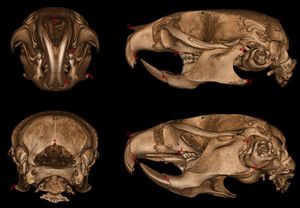

Publication: Mamm Genome. 2016 Dec;27(11-12):587-98. PMID: 27671791 | PDF Authors: Sabrautzki S, Sandholzer MA, et al. Institution: Institute of Experimental Genetics and German Mouse Clinic, Helmholtz Centrum Munich, German Research Center for Environmental Health (GmbH), Neuherberg, Germany. Background/Purpose: Animal models resembling human mutations are valuable tools to research the features of complex human craniofacial syndromes. This is the first report on a viable dominant mouse model carrying a non-synonymous sequence variation within the endothelin receptor type A gene (Ednra c.386A>T, p.Tyr129Phe) derived by an ENU mutagenesis program. The identical amino acid substitution was reported recently as disease causing in three individuals with the mandibulofacial dysostosis with alopecia (MFDA, OMIM 616367) syndrome. We performed standardized phenotyping of wild-type, heterozygous, and homozygous Ednra Y129F mice within the German Mouse Clinic. Mutant mice mimic the craniofacial phenotypes of jaw dysplasia, micrognathia, dysplastic temporomandibular joints, auricular dysmorphism, and missing of the squamosal zygomatic process as described for MFDA-affected individuals. As observed in MFDA-affected individuals, mutant Ednra Y129F mice exhibit hearing impairment in line with strong abnormalities of the ossicles and further, reduction of some lung volumetric parameters. In general, heterozygous and homozygous mice demonstrated inter-individual diversity of expression of the craniofacial phenotypes as observed in MFDA patients but without showing any cleft palates, eyelid defects, or alopecia. Mutant Ednra Y129F mice represent a valuable viable model for complex human syndromes of the first and second pharyngeal arches and for further studies and analysis of impaired endothelin 1 (EDN1)-endothelin receptor type A (EDNRA) signaling. Above all, Ednra Y129F mice model the recently published human MFDA syndrome and may be helpful for further disease understanding and development of therapeutic interventions. |

Landmarks of cephalometric/mandibular measurement. In total, eight datasets were evaluated by two experienced osteologists using the distance measurement tool of 3D Slicer 4.5 . Cranial and mandibular reference points on the bone surface were selected based on previously described landmarks (De Carlos et al. 2011). |